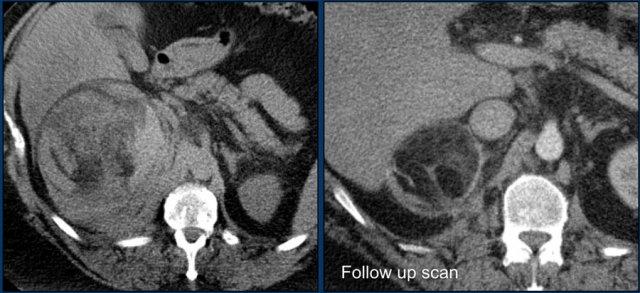

Hình ảnh cắt ngang và cắt vành cho thấy u tủy mỡ lớn bên phải kèm chảy máu.

Hình ảnh bên phải là phim chụp theo dõi.